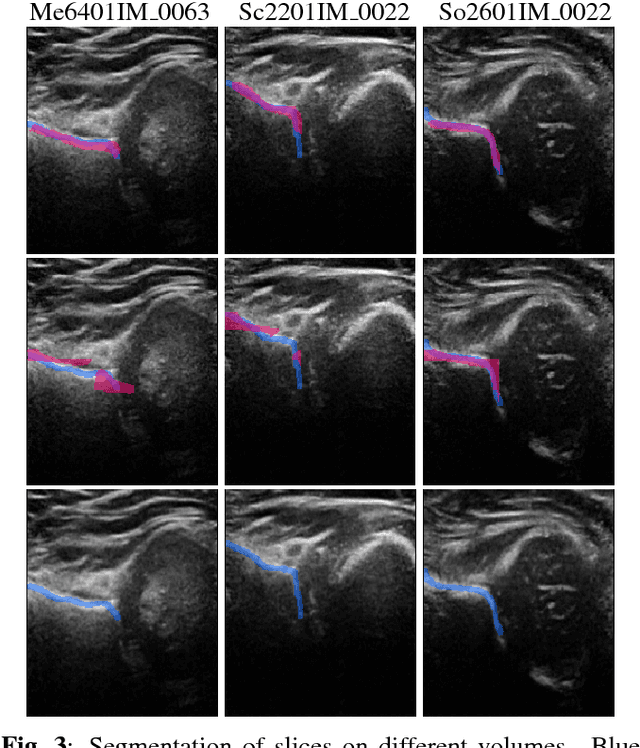

Abstract:We propose an end-to-end neural network that improves the segmentation accuracy of fully convolutional networks by incorporating a localization unit. This network performs object localization first, which is then used as a cue to guide the training of the segmentation network. We test the proposed method on a segmentation task of small objects on a clinical dataset of ultrasound images. We show that by jointly learning for detection and segmentation, the proposed network is able to improve the segmentation accuracy compared to only learning for segmentation.